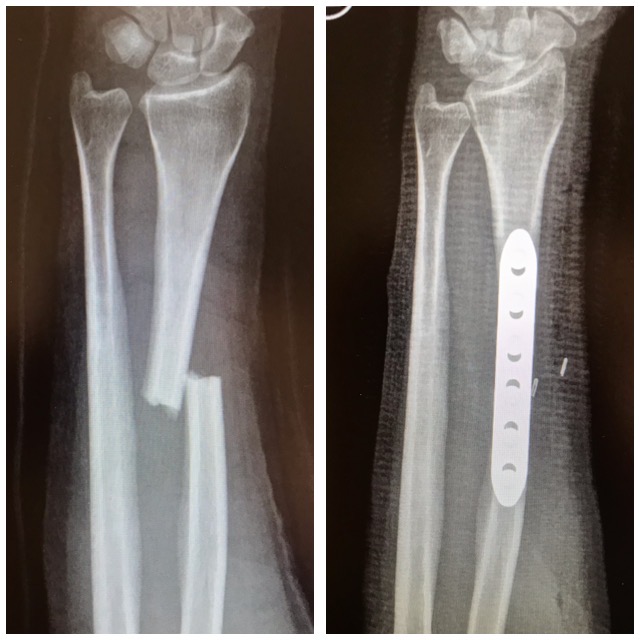

Kyynärvarsimurtuma

Ennen – jälkeen